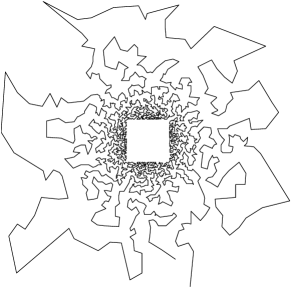

However, such sampling schemes are not performed along continuous lines and thus not physically plausible in MRI because of the constraints involved on the magnetic field gradient (magnitude and slew-rate). In [8], we have proposed a new approach to design continuous sampling trajectories based on the solution of Travelling Salesman Problem (TSP), as illustrated in Fig. 1(b). The specificity of this approach is that the empirical distribution of the trajectory can approximate any prescribed distribution . Such a curve is called a -Variable Density Sampler (-VDS). Unfortunately, continuity of the sampling trajectory is not a sufficient condition in MRI and it is not clear how to design admissible gradient waveforms to traverse such a trajectory.

| (a) | (b) |

|---|---|

|

|

To the best of our knowledge, the most efficient gradient design strategies consist of finding an admissible parameterization of a given curve by using optimal control [1, 2]. However, the main drawback of this approach is that the traversal of high curvature parts of the curve is rather slow. In the extreme case of angular points such as in TSP-based trajectories, it leads to extremely large acquisition time. In [9], we have proposed a new method to design magnetic field gradients by projecting any parameterized curve onto the set of hardware constraints. This method allows one to change the curve support and thus to yield faster traversal time.

The resulting solution has the same support as , which might be an important feature in some applications. The problems of this approach are: i) there is no control of the sampling density, especially in the high curvature parts of where samples tend to agglutinate and ii) there is no control over the total sampling time , which can be large if the trajectory contains singular points for instance (e.g., see Fig. 1(b)). These two drawbacks are illustrated in [9].

In the next part, we will emphasize that our algorithm enables to traverse VDS curves as depicted in Fig. 1(b) in a reasonable time, unlike optimal control-based reparemeterizations.